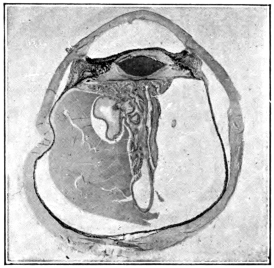

PLATE IV.

22.

LENS DISLOCATED BEHIND RETINA

curly bracket span

48

23.

FISTULA OF THE CORNEA

24.

CAPSULO-CORNEAL SYNECHIA

25.

RETINO-CORNEAL SYNECHIA

26.

SCLERAL FISTULA

27.

"    " (MAGNIFIED)